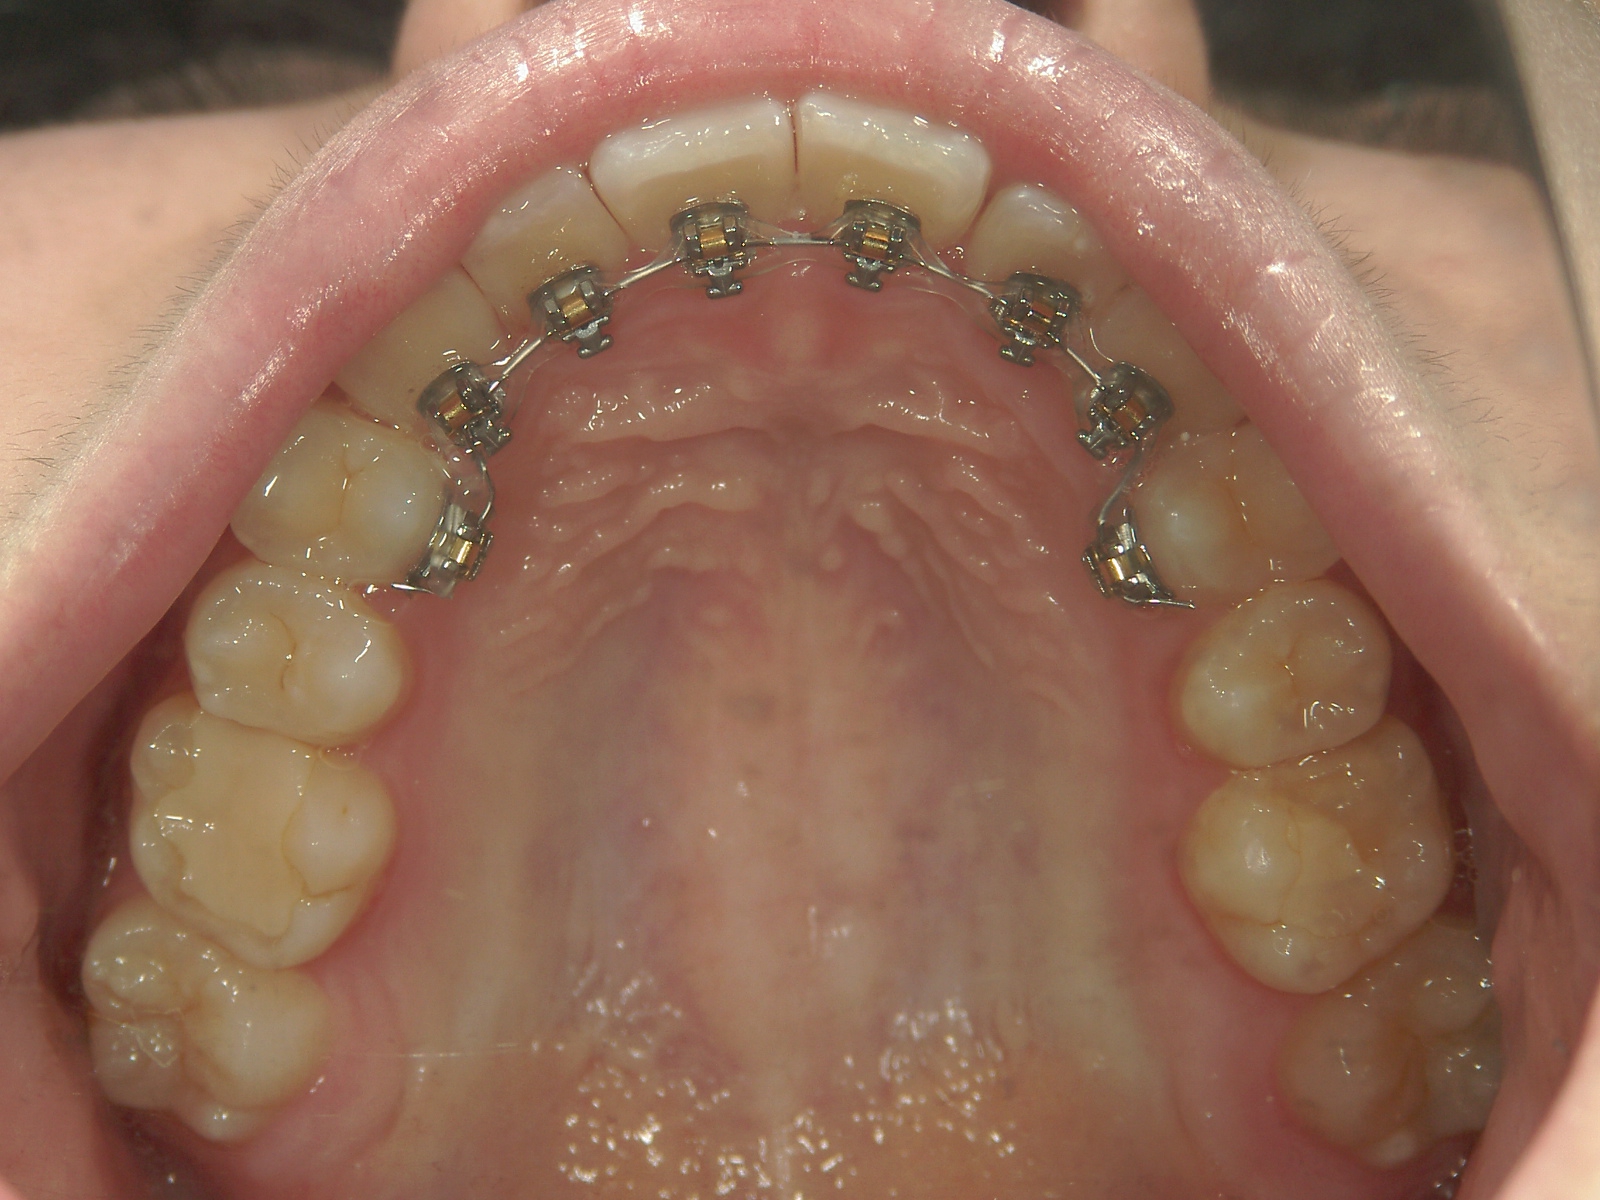

舌側プチワイヤー矯正/上顎のみ 症例(2)

13歳 女性 袋井市在住 治療期間 1年

矯正歯科 治療後 上顎